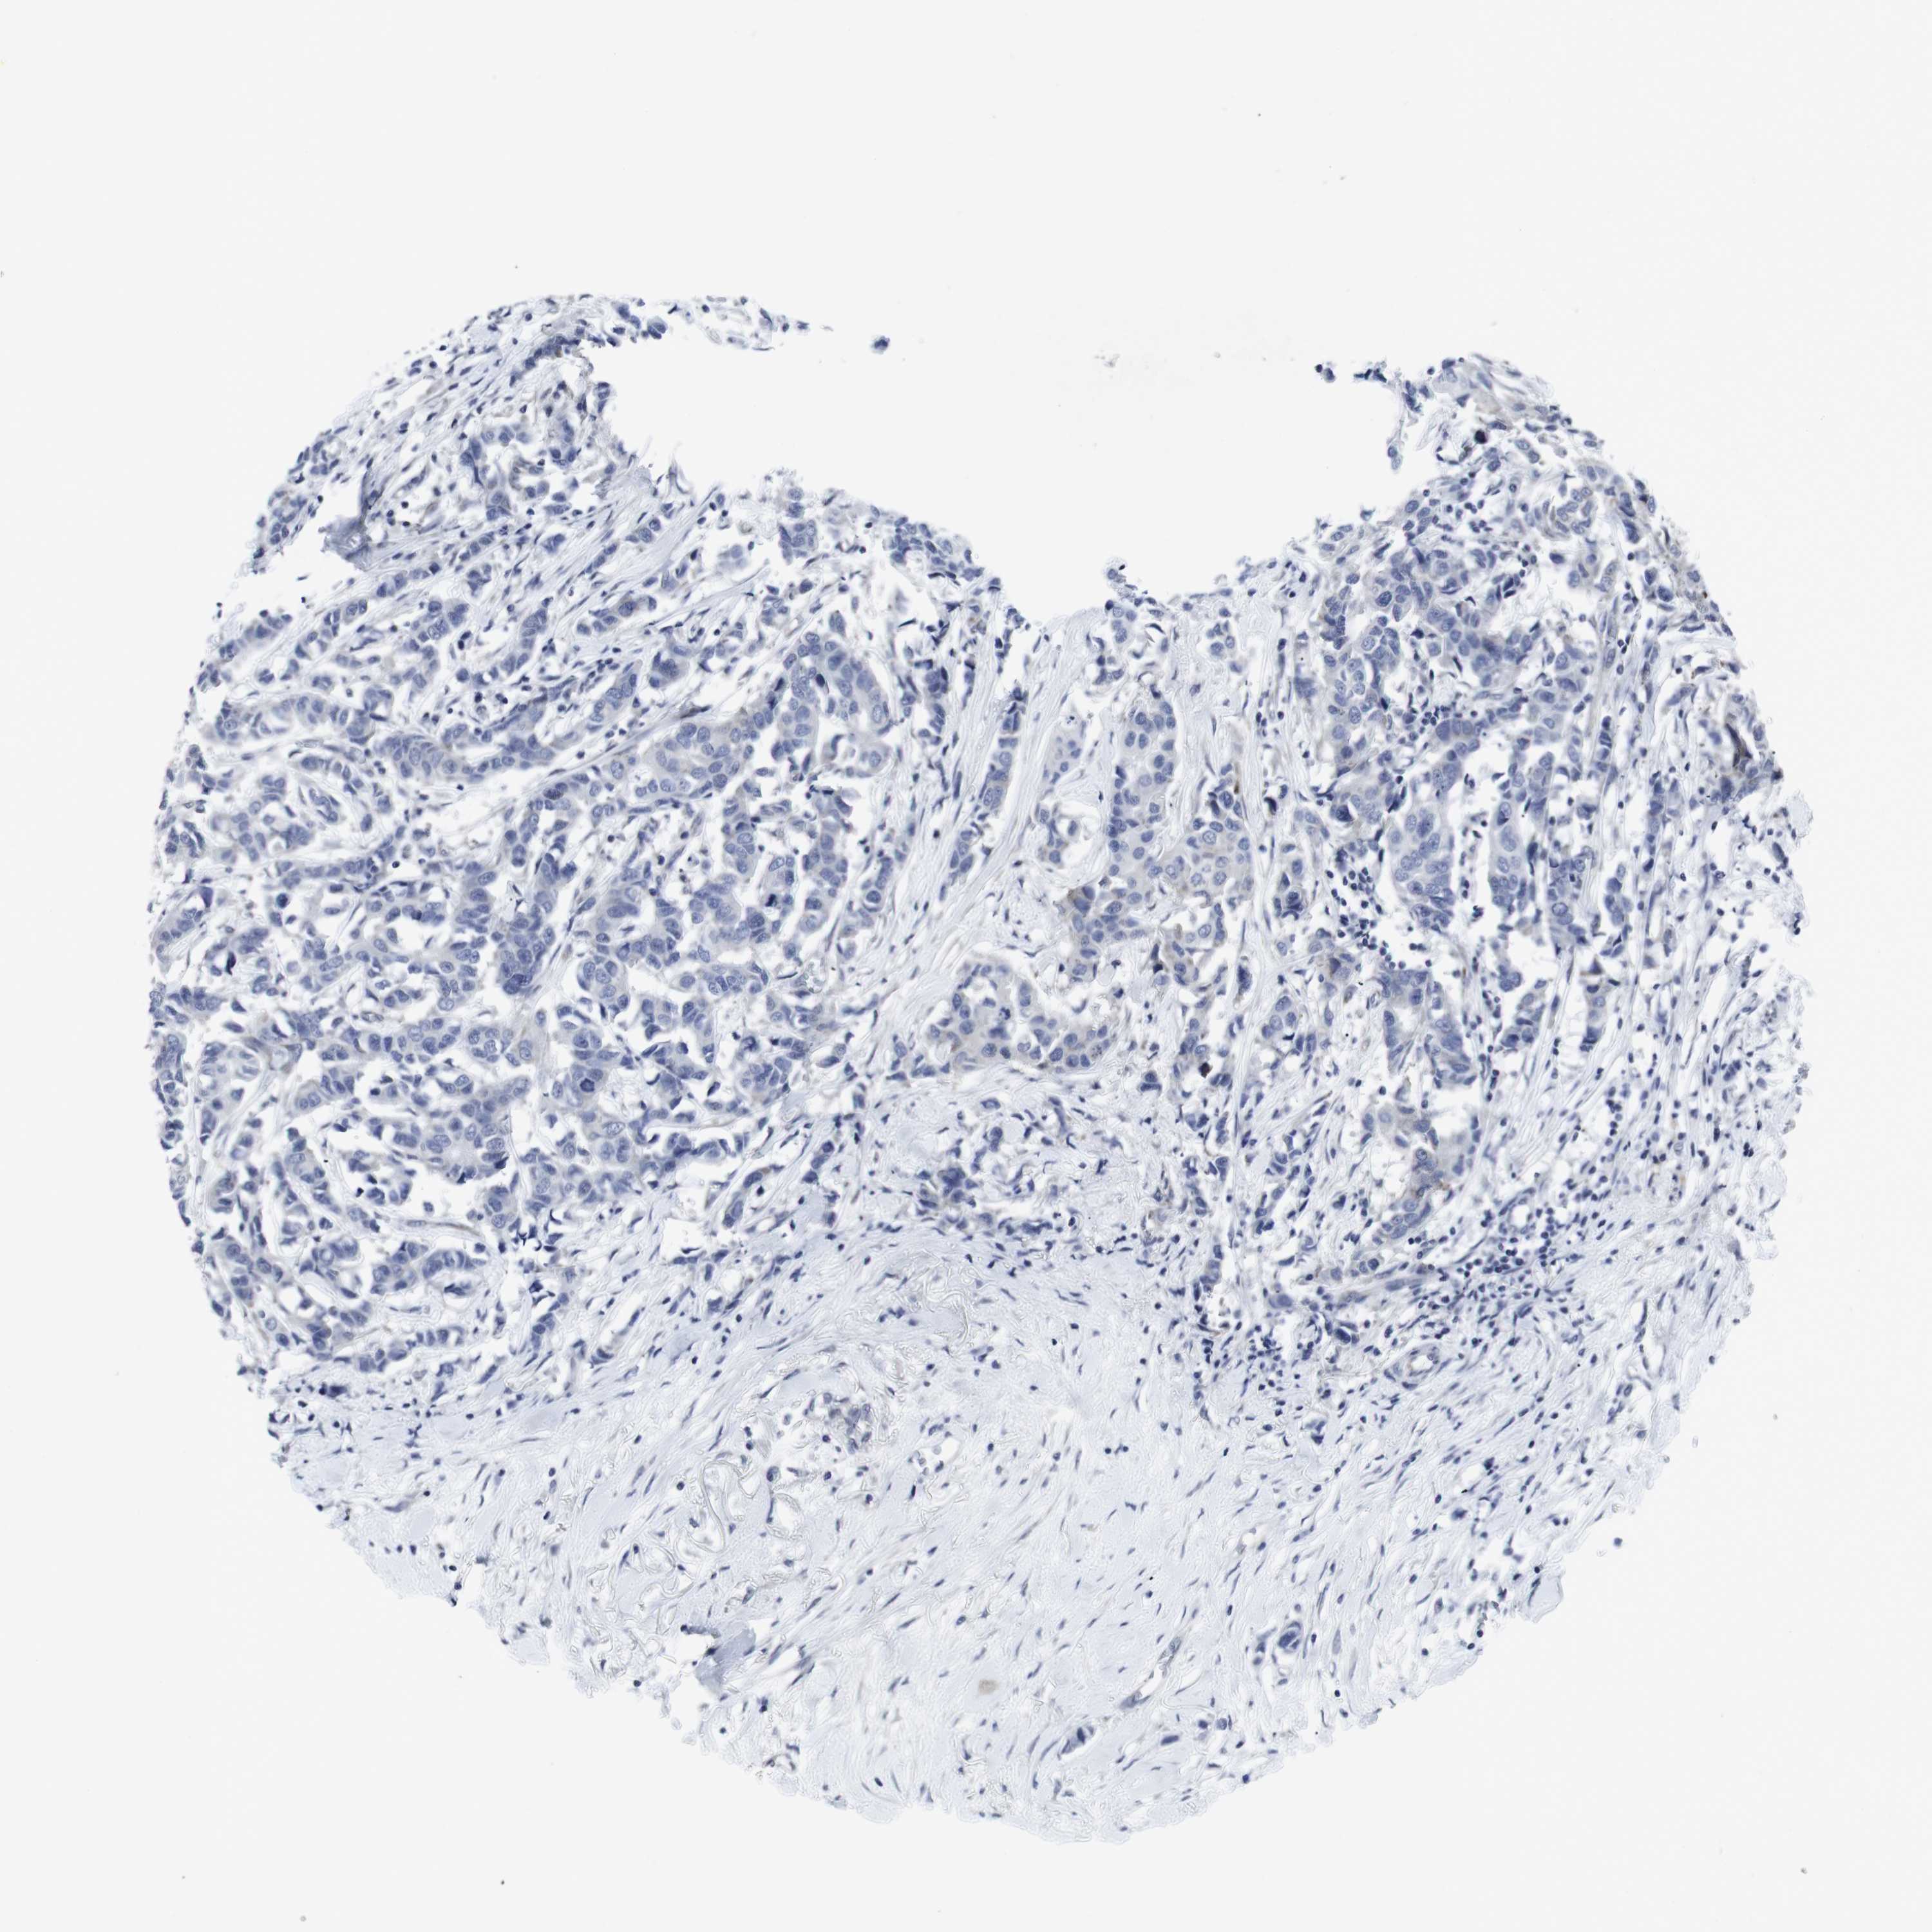

CANCER BREAST CANCER Show tissue menu

BRCA TCGA BRCA VALIDATION PROTEIN EXPRESSION

ANTIBODIES

AND

VALIDATION